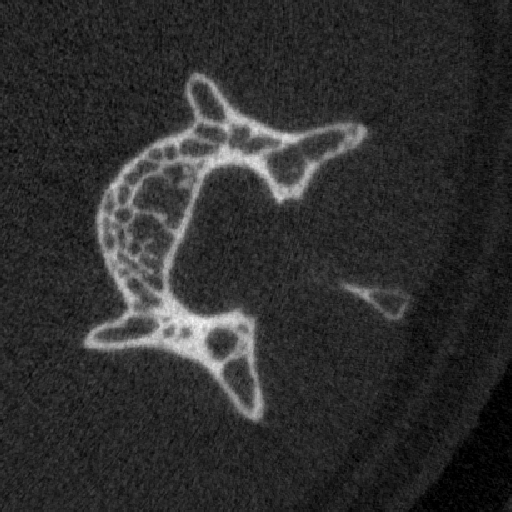

vivaCT80是SCANCO Medical AG 公司最新的活体产品,是vivaCT40和vivaCT75的升级产品,添加了触屏显示器、加热系统、呼吸麻醉接口,能够更好得监控动物的生存状态。vivaCT80的分辨率达到了3.9μm,样品仓也更大(90x500mm),配备大动物装置后可以扫描兔子头颅、四肢等体积较大的动物。研究对象通常为小鼠、大鼠或兔等活体小动物,麻醉或固定后扫描。可实现对组织、器官、生理功能代谢的纵向研究。